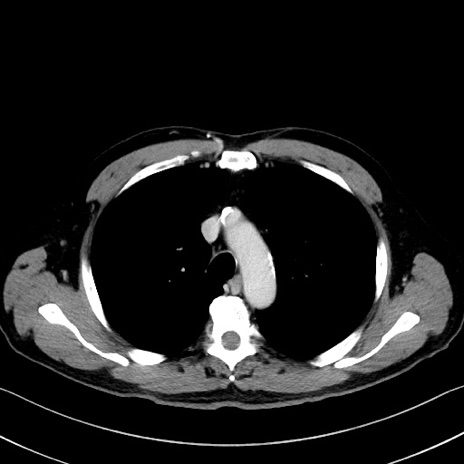

症例35(横断像)

【症例】70歳代 男性

【主訴】腹部膨満、嘔吐

【現病歴】昨日より腹部膨満感出現。本日増悪し、仙痛出現。嘔吐あり、受診。

【既往歴】糖尿病、胆摘後

【身体所見】BP 149/80mmHg、HR 74/min、BT 35.9℃、腹部:膨満、軟、圧痛なし。腸雑音減弱あり。上腹部正中切開瘢痕あり。

【データ】WBC 13500、CRP 1.72